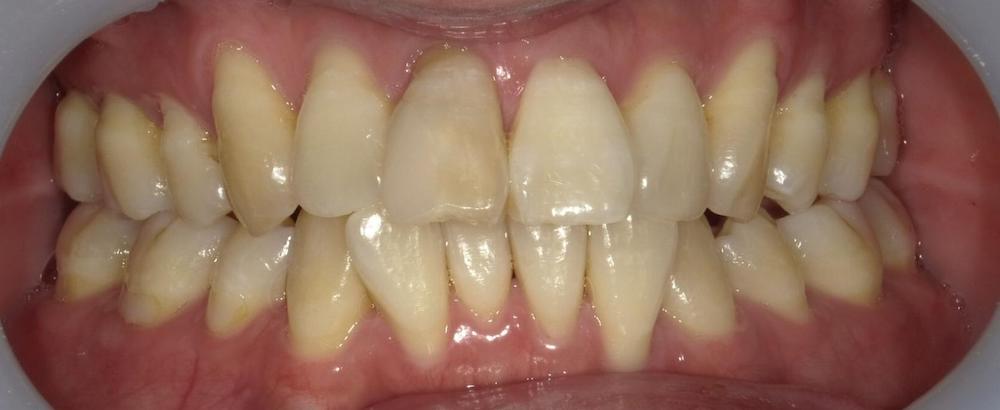

Before

症例1 前歯の歯並びが後戻りによって出てきてしまったしまったケース(中等度)

10年ほど前のワイヤー矯正後に、保定装置をつけていなかったことが原因で前歯が後戻りしています。

- 治療方法 インビザライン上下+形態修正

- 治療期間:1年

- 治療費用 ¥759000(税込)

- 治療のリスク・デメリット 保定装置をしないと後戻りする